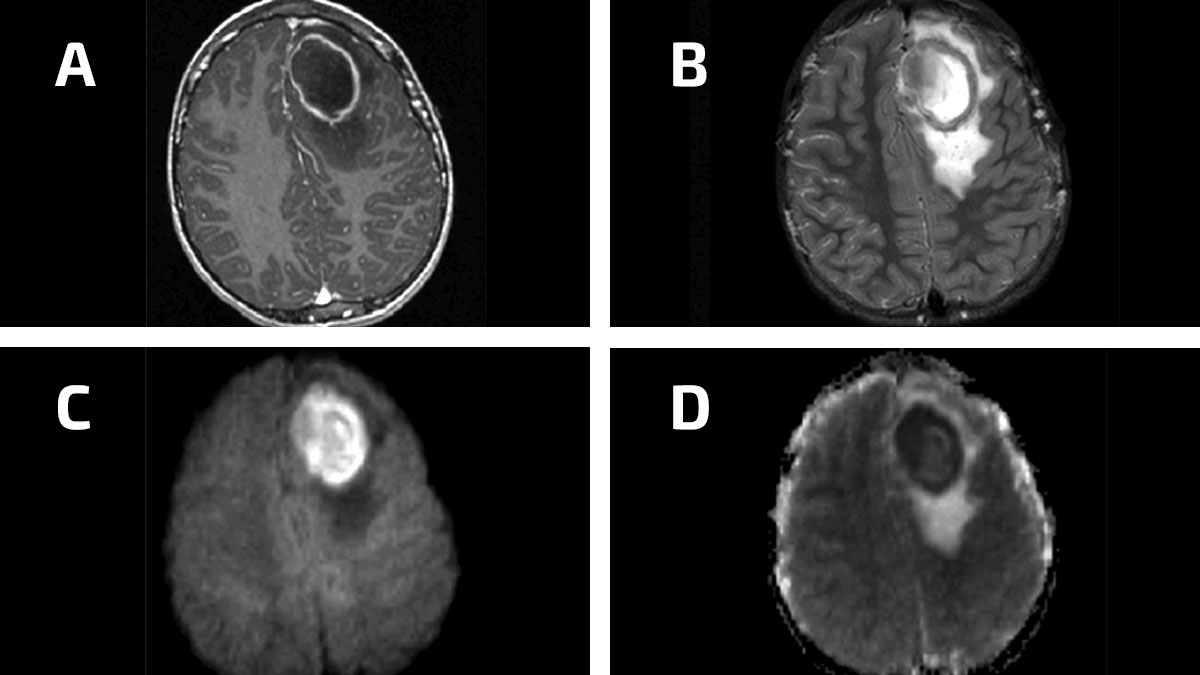

Aumentan casos de infecciones cerebrales en niños estadounidenses: CDC

Científicos estudian las misteriosas infecciones cerebrales que afectan algunos niños en Nevada